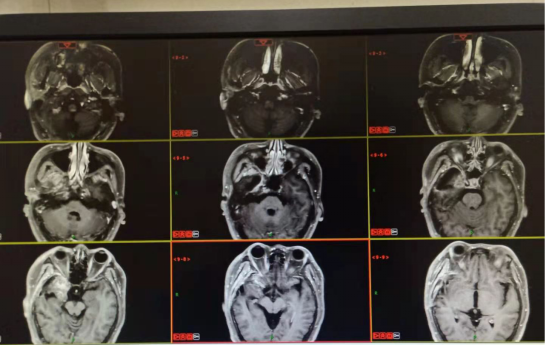

20200220三门峡黄河医院:右侧颞叶胶质瘤术后,右侧局部脑膜增厚,术区未见明显异常强化。

20200512三门峡市中心医院:右颞部胶质瘤术后改变,硬膜下积液。

2020.07.30三门峡市中心医院:右侧颞叶胶质瘤术后改变,右侧颞叶异常强化影,与0512日片对比强化灶较前明显,大小无明显变化。

2020.09.01右侧颞部胶质瘤术后改变,颞叶病灶强化程度较前减弱。左侧颞部结节状强化影,大致同前。